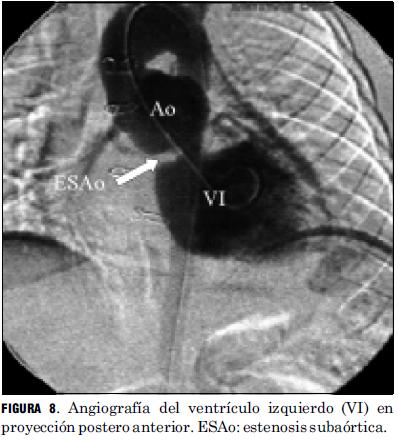

Las lesiones residuales significativas se presentaron en nueve pacientes (15%). Siete pacientes con estenosis supravalvular pulmonar, uno de ellos asociada a estenosis del origen de la arteria pulmonar rama izquierda, que requirieron angioplastia con balón (figuras 6 y 7), siendo efectiva en cuatro, mientras que en los otros tres requirió cirugía reparadora con la colocación de parche de pericardio bovino. Un paciente presentó una comunicación interauricular residual que debió ser cerrada quirúrgicamente, y otro paciente desarrolló una estenosis subaórtica (figura 8) que se resecó quirúrgicamente, todos con buena evolución (tabla 5).

La frecuencia de aparición de lesiones residuales significativas en nuestra serie fue similar a la publicada en la literatura, donde se refiere para la estenosis supravalvular pulmonar una incidencia de 5% a 30%, siendo menor su incidencia con el aumento de la experiencia del equipo. Son factores favorecedores de su aparición la corrección neonatal precoz, la existencia de un banding con larga evolución, la hipoplasia del anillo aórtico y la técnica quirúrgica empleada (16). En los casos de estenosis supravalvular pulmonar hemos tenido un porcentaje de éxito mediante la valvuloplastia con catéter balón, superior al promedio registrado en la literatura. Creemos que ello pueda deberse a múltiples variables a saber: técnica quirúrgica empleada, tamaño de muestra insuficiente para obtener conclusiones estadísticamente significativas. La aparición de una estenosis subaórtica significativa correspondió a un paciente que presentó una leve estenosis subpulmonar previo a la realización del switch arterial, subvalorada en el momento de la realización de dicha técnica.